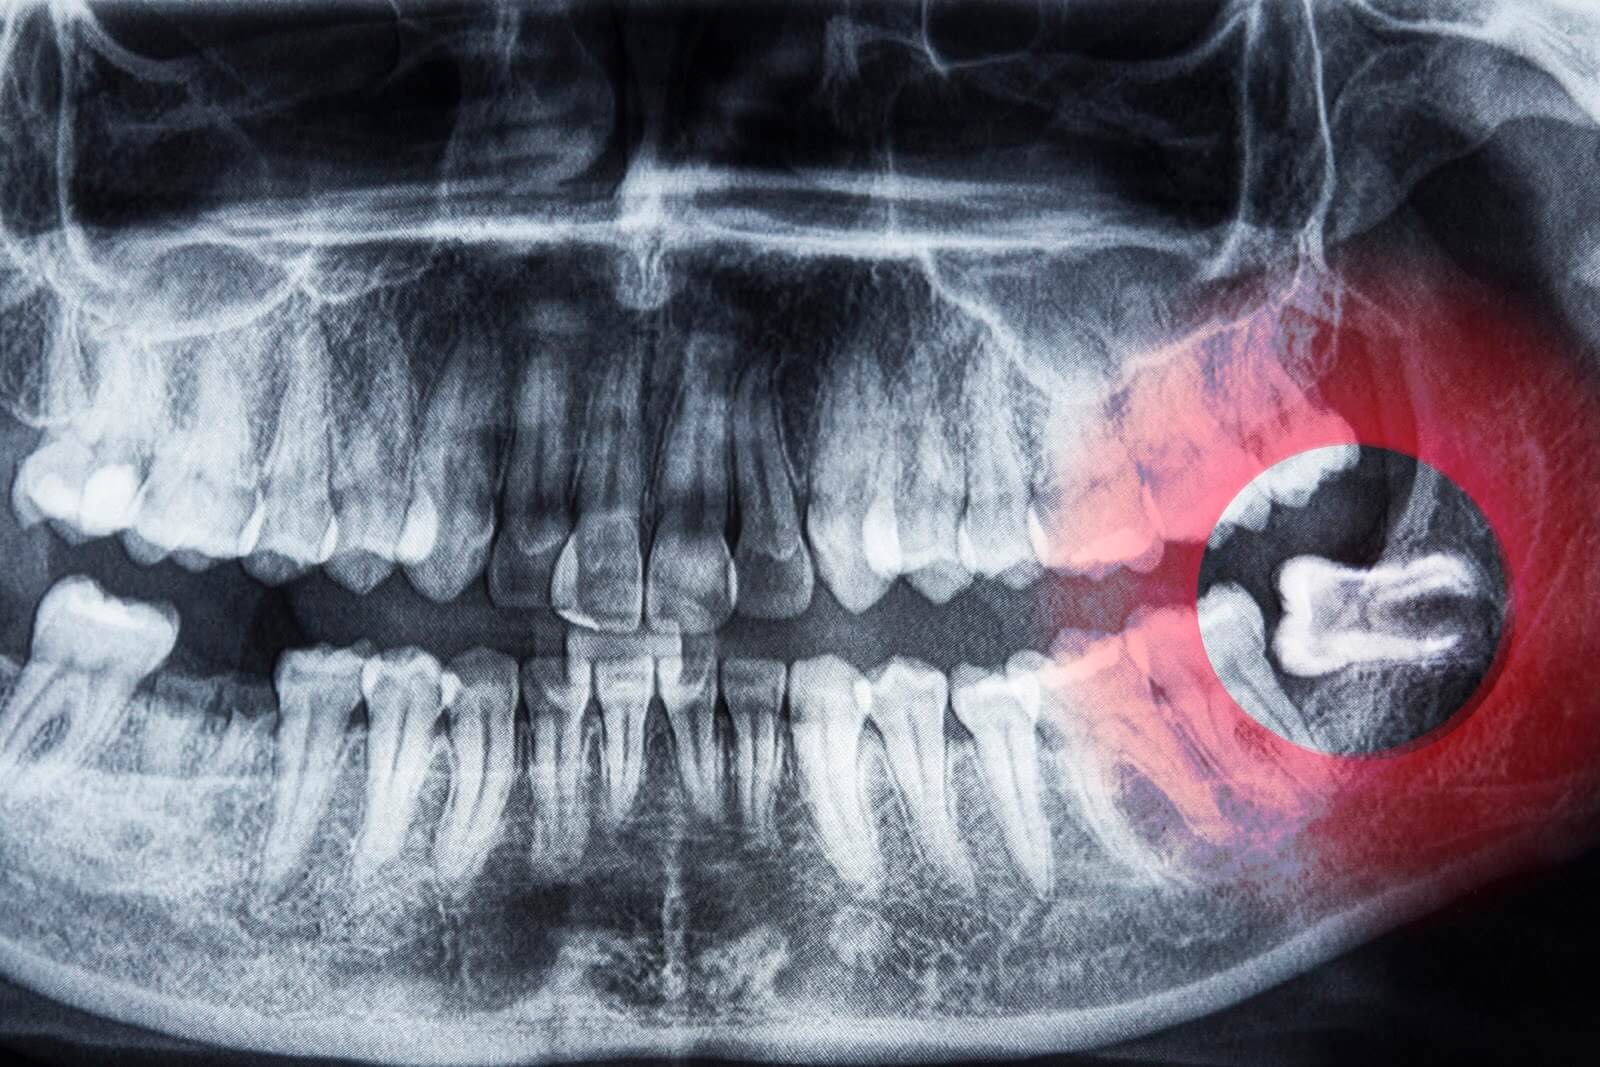

Horizontal Inflamed Wisdom Tooth On Panoramic Dental Tooth X-ray

www.dreamstime.comWISDOM TOOTH, X RAY Stock Photo - Alamy

www.dreamstime.comWISDOM TOOTH, X RAY Stock Photo - Alamy

www.cigna.comX-ray Oral Image With An Inflamed Wisdom Tooth Close-up Stock Photo

www.cigna.comX-ray Oral Image With An Inflamed Wisdom Tooth Close-up Stock Photo